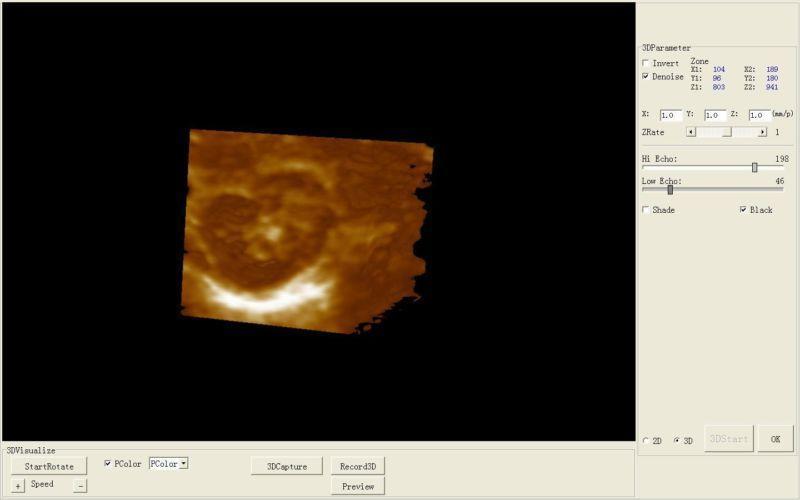

Model: HIGH RESOLUTION

Display modes: B, B+B, B+M, M, 4B

Pseudo color processor: 7 colors